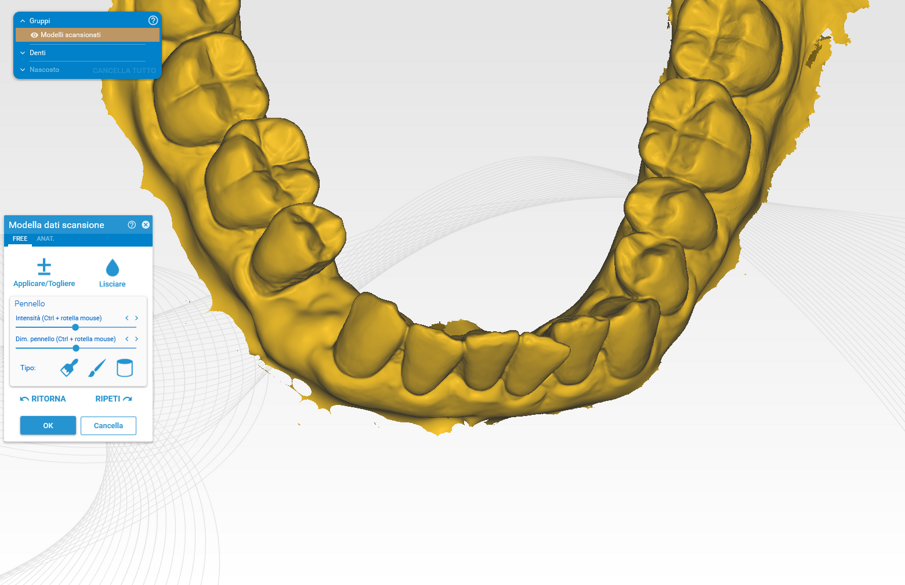

Prima dell’estrazione (S0), ad ogni paziente è stata eseguita una scansione intraorale tramite scanner iTero (Align Technology) (Fig. 2), e le scansioni sono state archiviate. A distanza di 2 mesi dall’estrazione è stato creato un lembo vestibolare a busta, a mezzo spessore, è stato inserito l’impianto nel sito (Figg. 3, 4) ed è stata posizionata la matrice in collagene suino volumetricamente stabile Geistlich Fibro-Gide (Geistlich Pharma), stabilizzandola al periostio con due punti di sutura riassorbibili interni (Fig. 5)7. Il lembo è stato quindi suturato con suture non riassorbibili e punti sospesi in modo da garantire la chiusura primaria e mantenere la matrice sommersa ma non compressa (Fig. 6).

6 giorni con una compressa ogni 12 ore e sciacqui di clorexidina 0,2%. A distanza di 15 gg sono state eliminate le suture e dopo 3 mesi dall’inserimento dell’impianto e della matrice in collagene (S1) è stata eseguita una seconda scansione (Fig. 7). A distanza di un anno (S2) è stata eseguita l’ultima scansione (Figg. 8-10).

Ogni gruppo di scansione per ogni paziente è stato elaborato tramite exocad e analizzato confrontando S0 con S1 (valutazione a tre mesi) e S0 con S2 (valutazione a un anno) (Figg. 11, 12). La valutazione del perimetro di interesse riguarda una zona trapezoidale situata nella parte innestata che si dilata da un’ipotetica linea di congiunzione dei margini dei denti adiacenti e si estende fino alla linea mucogengivale e lateralmente alle aree interprossimali.